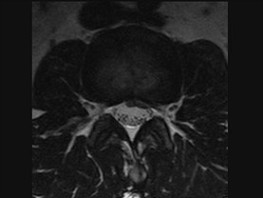

腰椎间盘突出症(如图1)与腰椎管狭窄症(如图2)临床症状的主要不同点为()